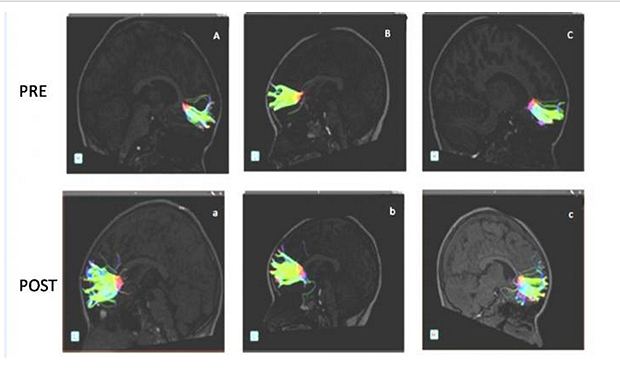

El tejido cerebral del menor de 2 años 'avisa' de potenciales trastornos